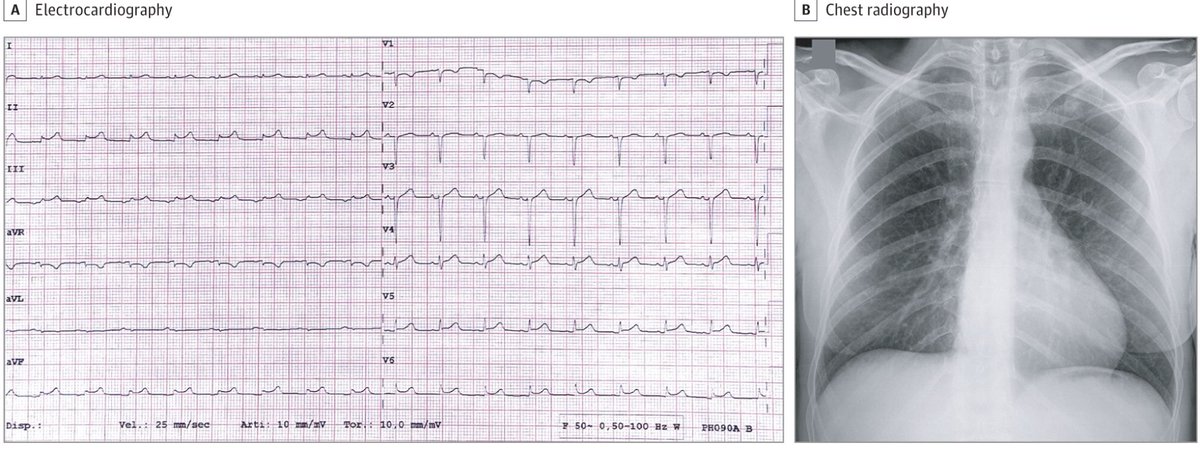

3/ كشف رسم القلب الكهربائي عن إيقاع القلب الخطير. كان لدى المريض مستويات عالية من الدم من بروتين يسمى تروبونين ، وهو علامة على تلف عضلة القلب. اندفع الأطباء للعمل على اعادة فتح الشرايين المسدودة للمريض - لكنهم اكتشفوا أنه لا توجد شرايين مسدودة.

14/ الكثير منهم ليس لديه تاريخ سابق مع مرض من أمراض القلب. ولكن اغلبهم وجدنا لديه مخططات كهربائية غير طبيعية للقلب ، مثل مريض بروكلين ، بالإضافة إلى مستويات مرتفعة من التروبونين ، والتي ارتفعت في بعض الأحيان إلى المستويات المشاهدة في المرضى الذين يعانون من الأزمات القلبية.

17/ مثل المريض في بروكلين ، كان مخططها الكهربائي غير طبيعي ، وكان لديها مستويات عالية من التروبونين في دمها. بسبب تفشي فيروس #كورونا في إيطاليا ، قرر الأطباء أن يجروا لها اختباراً ووجدوا أنها مصابة.